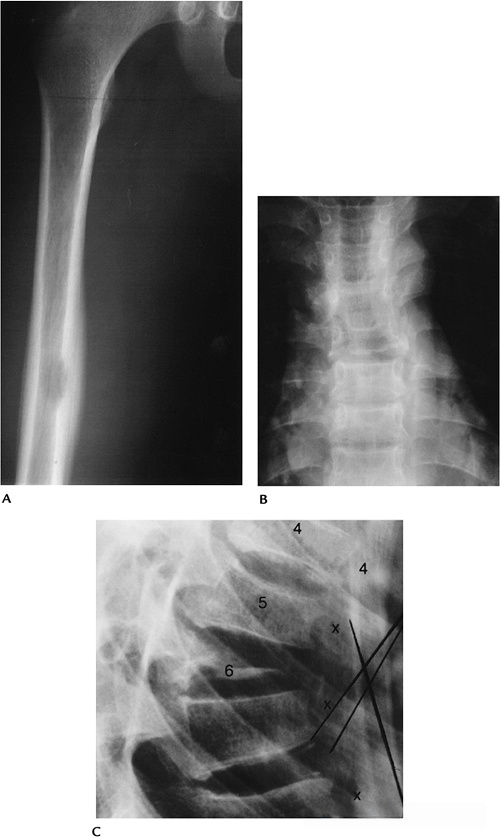

7a1720be8baf1259e6575c4ff03a3773.png

图-13  75岁男性因使用糖皮质激素导致的骨质疏松。(A)矢状位T2显示椎体压缩,信号减低和增高混合。(B)SE-DWI显示一个高信号区(箭头),这是由肺部转移引起的。

fba59273f7a0d4393edd5a753f4207d2.png

(A) 六个月前,胸椎矢状位 T2 加权 MRI 显示 T9 和 T12 急性压缩性骨折。

(B) 椎体后凸成形术后,腰椎矢状位 T2 MRI 显示 T8 、 T10 和 T11 处急性压缩性骨折,T9和 T12 处有明显的骨折线。